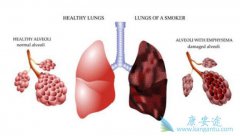

�������˵�ΰ��ǹ���������һ���������ΰ�ת��������������һ����������֯ÿ����ѪҺ���ͷŰ�ϸ��������İ�ϸ����ѪҺ���ܰ�����ȫ����һ���������죬ɢ��İ�ϸ����������һ����������κ���֯������ֲ����Ѹ�������������ƻ��������ܣ����յ��²��� ...

�����ΰ���ת��ʱ����ϸ���������Ĺ���֯�����ƻ���ʹ���ƹ�ϸ���ͷ�ϸ�����ӱ�������������ܹǷ�Ӧ������ܹǷ�Ӧ�������ƹ�ϸ����Ծ���ƻ��ǵ������ṹ�����¹��ܽ⡣ �ΰ���ת�� ��� ���ԣ��������50�����ϡ��÷����߹ǡ����������輰�ǣ���� ...